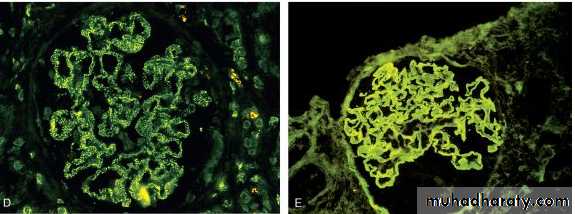

The best –characterized disease in this group is anti-GBM antibodies. It results from the formation of autoantibodies directed against the GBM. Deposition of these antibodies creates a linear pattern of staining when visualized by I.F.M . this is in contrast with granular pattern described for other forms of immune complex-mediated nephritis. Sometimes the anti- GBM antibodies cross react with the basement membranes of the lung alveoli, result in combined lung and kidney lesions (Goodpasture syndrome).

Planted antigens also include DNA bacterial products, aggregated IgG which deposit in the mesangium because of their size. Most of these planted Ags induce a granular pattern of immunoglobulin deposition as seen by I.F.M

T cell- mediated injury may account for some cases of GN in which either there are no deposits of Ab or immune complexes or the deposits do not correlate with the severity of damageFIGURE 20-4 Antibody-mediated glomerular injury can result either from the deposition of circulating immune complexes (A) or, more commonly, from in situ formation of complexes exemplified by anti-GBM disease (B) or Heymann nephritis (C). D and E, Two patterns of deposition of immune complexes as seen by immunofluorescence microscopy: granular, characteristic of circulating and in situ immune complex nephritis (D), and linear, characteristic of classic anti-GBM disease (E).